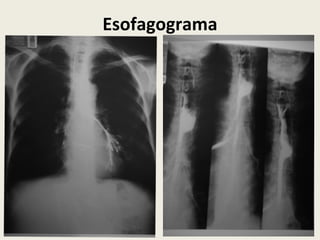

O documento descreve o caso de uma paciente de 54 anos com estenose do esôfago e fístula esôfago-brônquica devido a câncer de esôfago e ingestão de soda cáustica no passado, que apresenta tosse e disfagia. A proposta é realizar uma abordagem endoscópica para tratar a estenose e fístula.